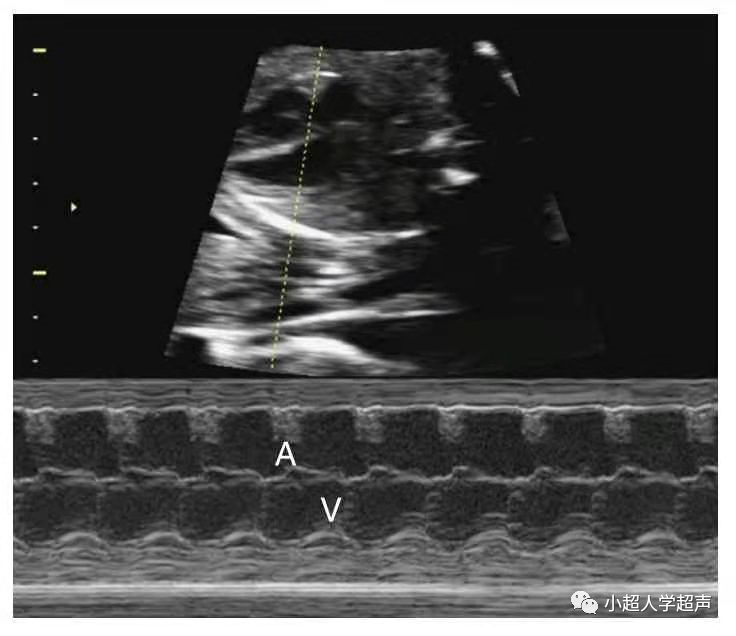

3)三度房室传导阻滞

完全性房室传导阻滞(CAVB)是指胎儿心室率<80/min,心房律>心室律,心房壁和心室壁运动曲线节律分离、互不相关,即心房、心室各跳各的,为完全性房室传导阻滞。